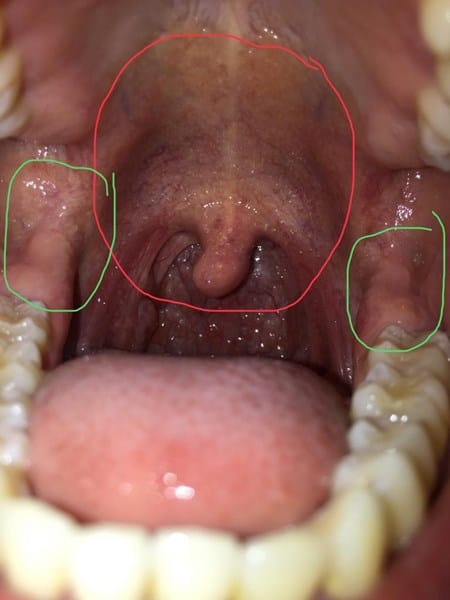

I. Hola Compañer@, aunque no soy dermatólogo ni médico creo que parece tratarse de una granulomatosis faríngea, un tipo de infección que en principio se trata con antibióticos específicos, aquí podemos una captura e información sobre el cuadro.

Si lo deseas y es posible podrías solicitar un cultivo de tejido (biopsia) de nuevo en tu médico, es una prueba que sólo consiste en tomar una muestra mínima de tejido de la zona afectada para analizarla, de esta forma puede saberse con certeza el porqué de estos granos, y de las molestia local en la lengua.

Tambien, ya en menor grado, podrían ser petequias, causadas por lo general al padecer una carencia de alguna vitamina en concreto, o bien por una serie de alteraciones en la sangre,

Creo que un cuadro llamado 'púrpura trombocitopénica', está derivado -o asociado- a este trastorno, con un aspecto un poco más cercano o fiel al que nos describe,